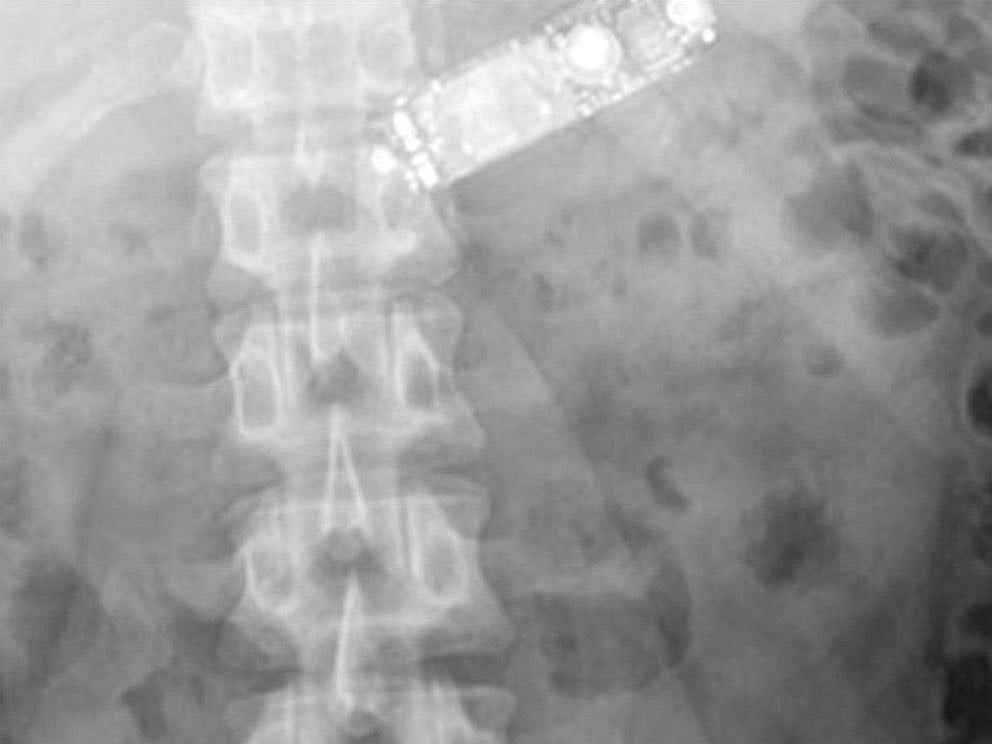

இந்த நிலையில் சோதனை முடிந்த சில மணி நேரங்களுக்கு பிறகு குவாஷிகர் அலி கடுமையான வயிறு வலியால் துடித்துள்ளார். இதனால் அவர் மருத்துவமனைக்கு கொண்டு செல்லப்பட்டார். அங்கு அவரை சோதனை செய்தபோது, அவரது வயிற்றுக்குள் எதோ பொருள் ஒன்று உதிரி பாகங்களாக கிடந்தது தெரியவந்தது.

பின்னர் இதுகுறித்து குவாஷிகர் அலியிடம் கேட்டபோது, அவர் போலீஸ் சோதனைக்கு பயந்து தான் வைத்திருந்த செல்போனை விழுங்கியதாக தெரிவித்தார். மேலும் அதனை கடித்து விழுங்கியதாக தெரிவித்தார். இதனை கேட்டதும் மருத்துவர்களும், காவல்துறை அதிகாரிகளும் அதிர்ச்சியடைந்தனர். இதையடுத்து அவருக்கு அறுவை சிகிச்சை செய்யப்பட்டு உதிரி பாகங்கள் நீக்கப்பட்டுள்ளது.